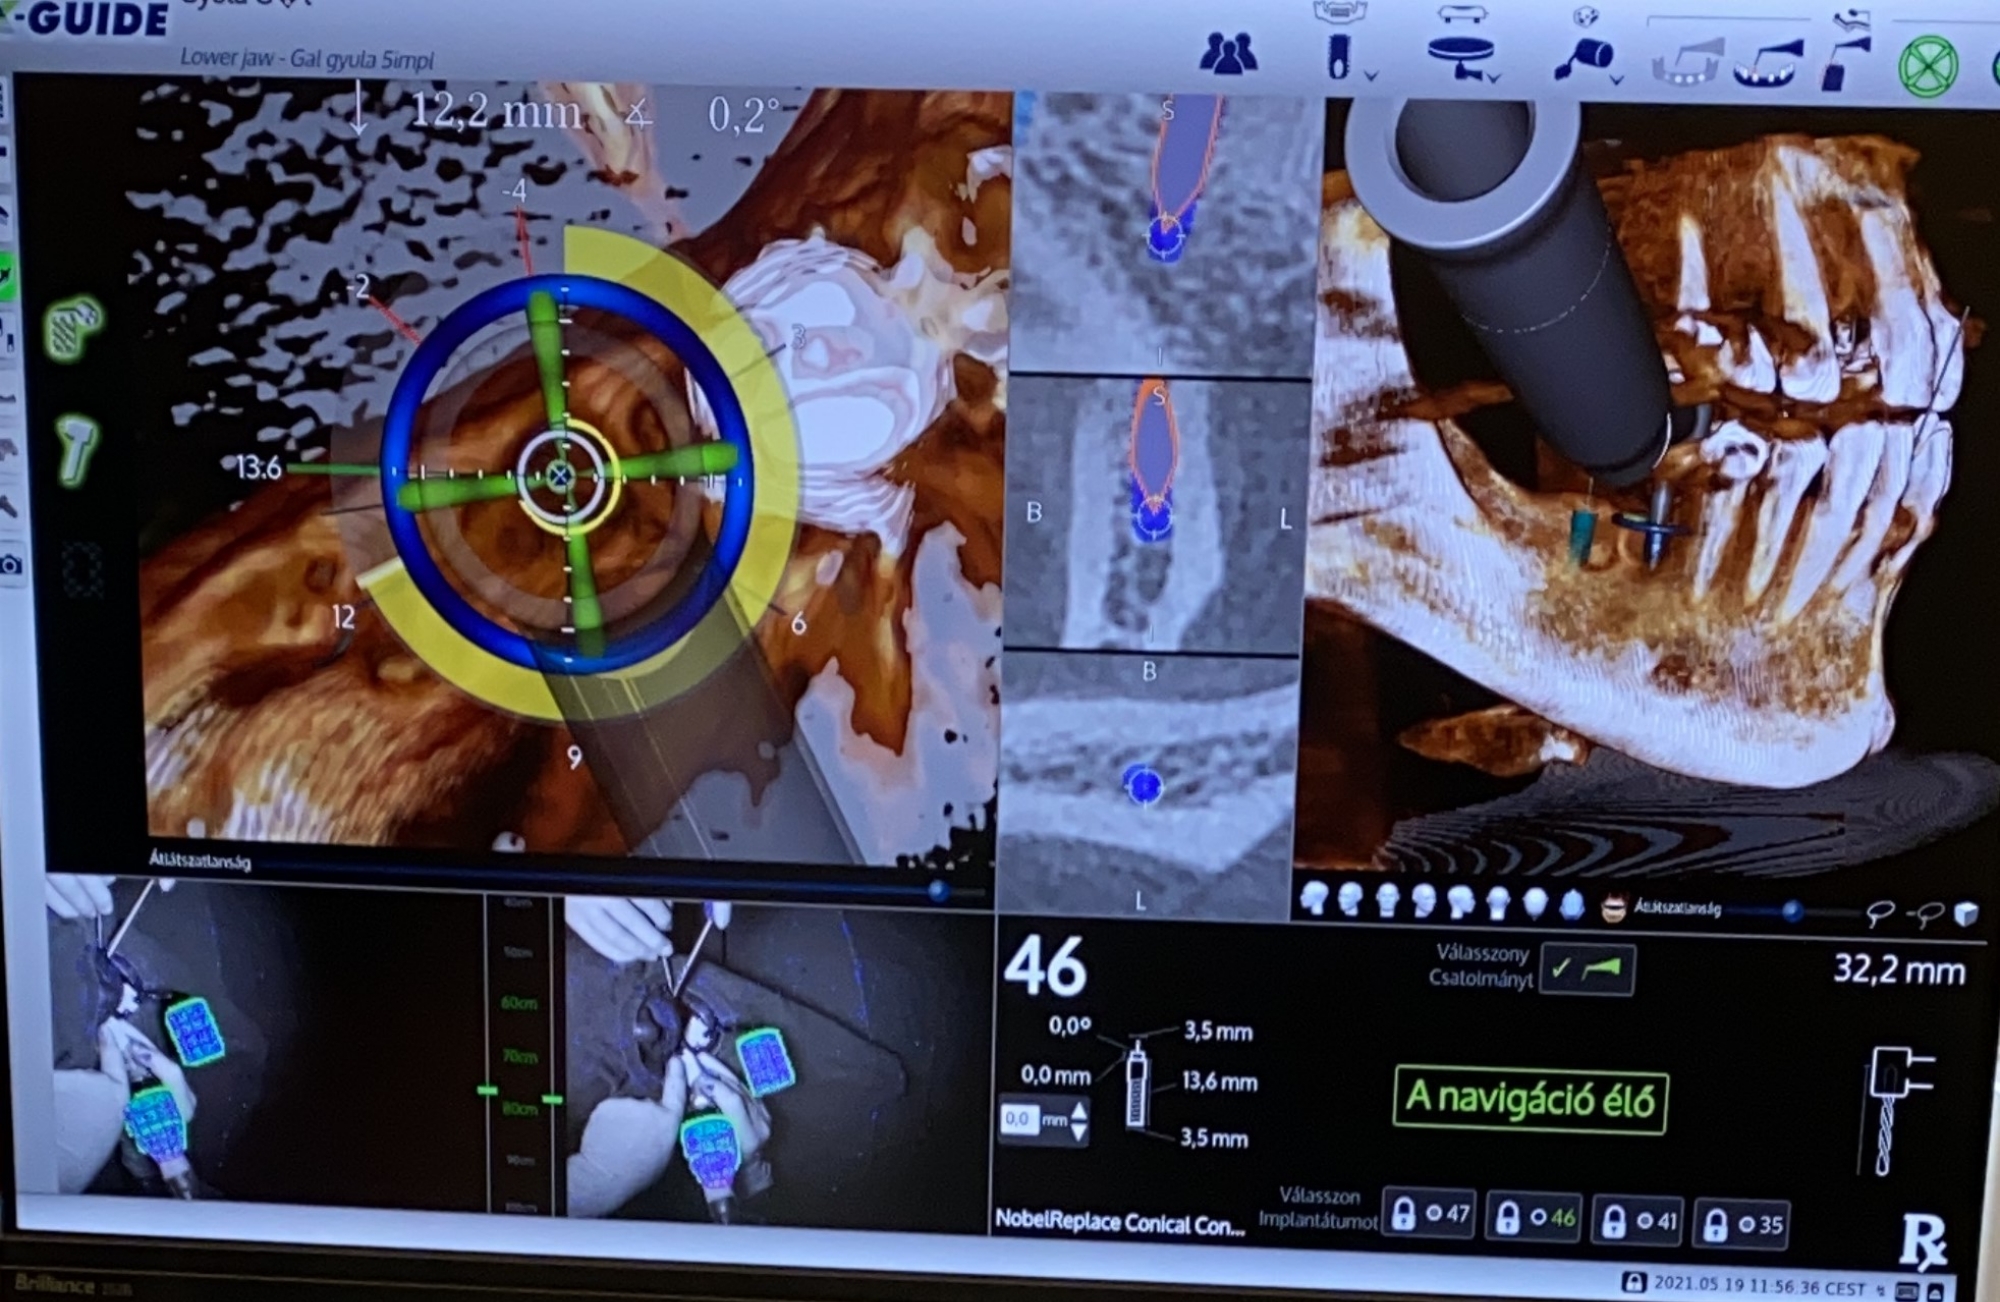

Calibration In Dynamic Navigation Surgery In Implamt

Browse our specialized Calibration In Dynamic Navigation Surgery In Implamt portfolio with numerous expertly curated photographs. optimized for both digital and print applications across multiple platforms. providing reliable visual resources for business and academic use. Each Calibration In Dynamic Navigation Surgery In Implamt image is carefully selected for superior visual impact and professional quality. Perfect for marketing materials, corporate presentations, advertising campaigns, and professional publications All Calibration In Dynamic Navigation Surgery In Implamt images are available in high resolution with professional-grade quality, optimized for both digital and print applications, and include comprehensive metadata for easy organization and usage. Our Calibration In Dynamic Navigation Surgery In Implamt collection provides reliable visual resources for business presentations and marketing materials. Whether for commercial projects or personal use, our Calibration In Dynamic Navigation Surgery In Implamt collection delivers consistent excellence. The Calibration In Dynamic Navigation Surgery In Implamt archive serves professionals, educators, and creatives across diverse industries. Regular updates keep the Calibration In Dynamic Navigation Surgery In Implamt collection current with contemporary trends and styles. Advanced search capabilities make finding the perfect Calibration In Dynamic Navigation Surgery In Implamt image effortless and efficient. Multiple resolution options ensure optimal performance across different platforms and applications.